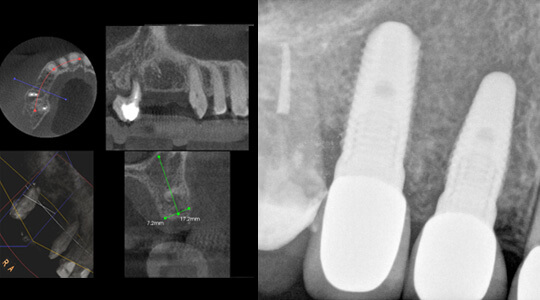

Zahnlücke im Oberkiefer, zwei Zähne fehlen. Die Nachbarzähne sind für eine Brückenversorgung ungeeignet.

Nach der Röntgenuntersuchung und Vermessung des Knochenangebotes erfolgte eine Insertion von zwei Implantaten, d. h. künstlichen Zahnwurzeln. Nach einer Einheilzeit von 4 Monaten konnten die Zahnkronen hergestellt werden.